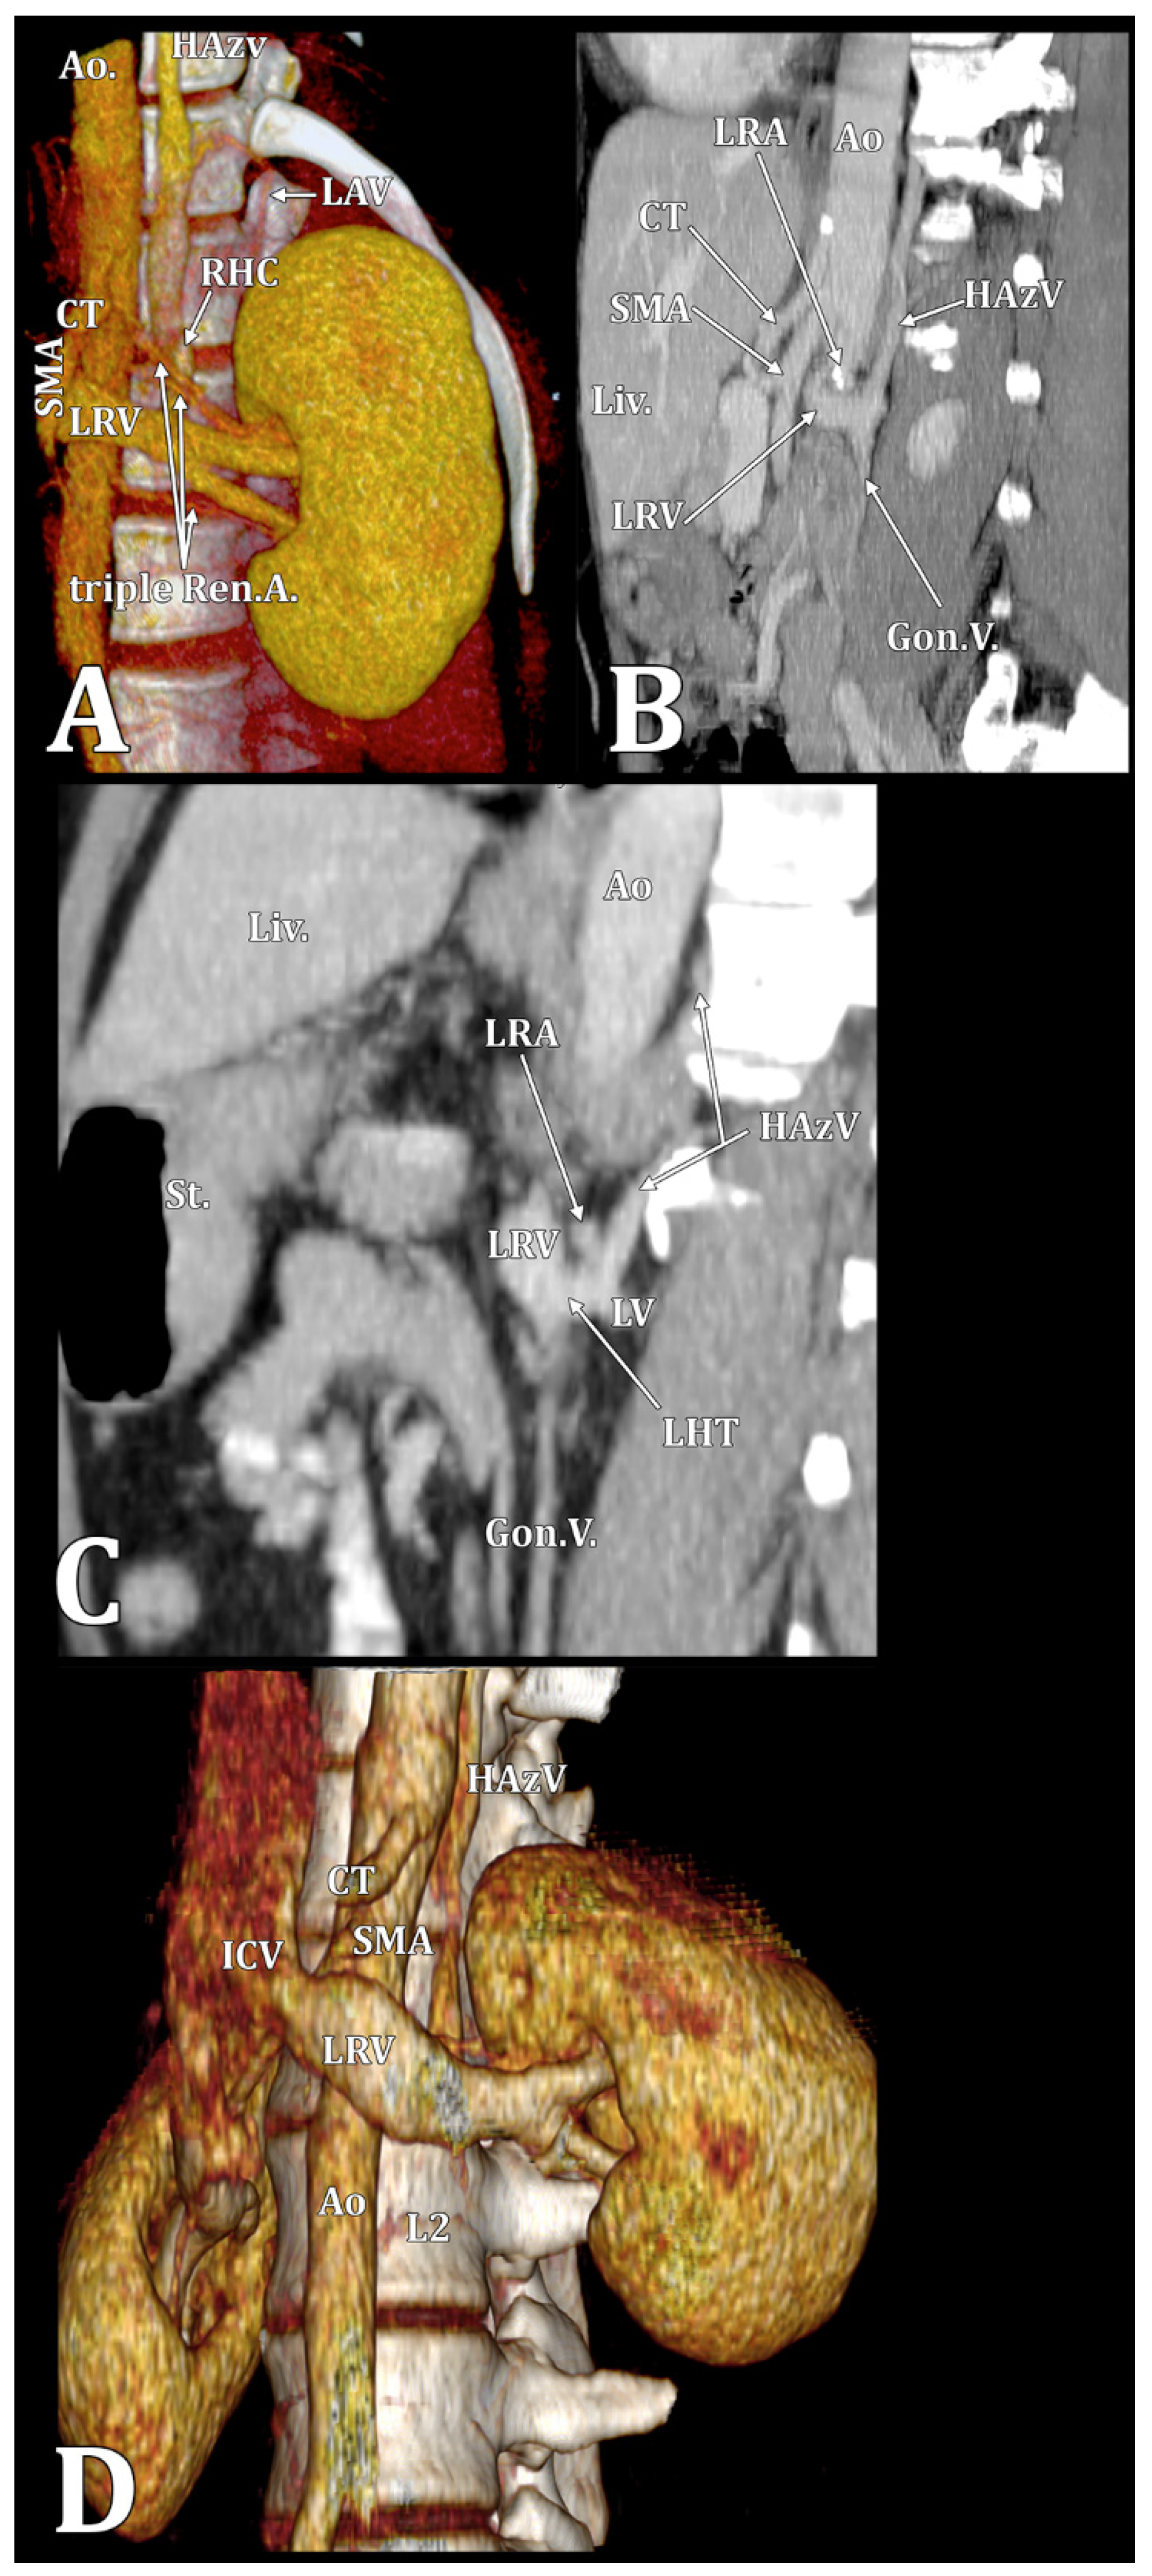

| ALV | ascending lumbar vein |

| HAzV | hemiazygos vein |

| LRV | left renal vein |

| RHC | reno-hemiazygos connection |

| RLRV | retroaortic left renal vein |

| Type 1 | Type 2 | |

|---|---|---|

| M | 2/4 (50%) | 2/4 (50%) |

| 2/85 (2.35%) | 2/85 (2.35%) | |

| F | 9/10 (90%) | 1/10 (10%) |

| 9/65 (13.84%) | 1/65 (1.53%) |

| LRV | LRV/RP | RLRV | CLRV | |

|---|---|---|---|---|

| Type 1 (11 cases) | 7 (63.64%) | 1 (9.09%) | 1 (9.09%) | 2 (18.18%) |

| Type 2 (3 cases) | 2 (66.67%) | – | – | 1 (33.33%) |

| L1/L2 Disc | L2 | L2/L3 Disc | L3 | |

| Type 1 (11 cases) | 1 (9.09%) | 5 (45.46%) | 3 (27.27%) | 2 (18.18%) |

| Type 2 (3 cases) | – | 1 (33.33%) | – | 2 (66.67%) |